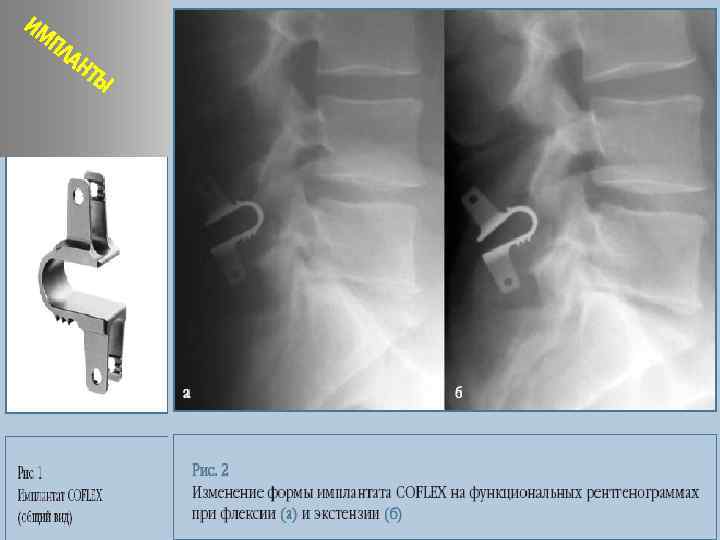

Динамическая система стабилизации

ИМ ПЛ АН ТЫ